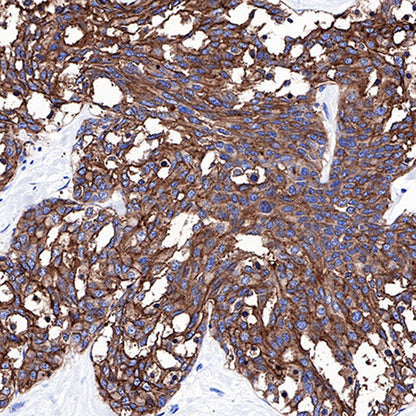

IHC shows positive staining in paraffin-embedded human breast cancer. Anti-CEA(CD66e) antibody was used at 1/1000 dilution, followed by a Goat Anti-Rabbit IgG H&L (HRP) ready to use. Counterstained with hematoxylin. Heat mediated antigen retrieval with Tris/EDTA buffer pH9.0 was performed before commencing with IHC staining protocol.